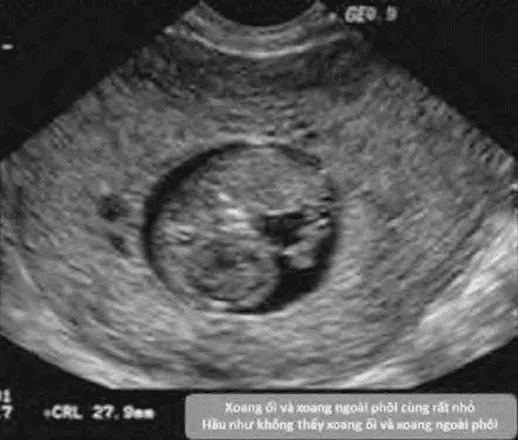

- Không có màng ối rõ sau 6 tuần vô kinh.

- Không thấy phôi sau 6 tuần vô kinh.

- Yolk-sac giãn > 7 mm.

- (MSD - CRL) < 5 mm.

- Xoang ối giãn rộng (expanded amnion sign).